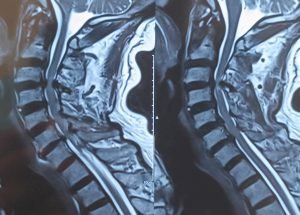

Expert spine services including minimally invasive surgery, pain management, and deformity correction.